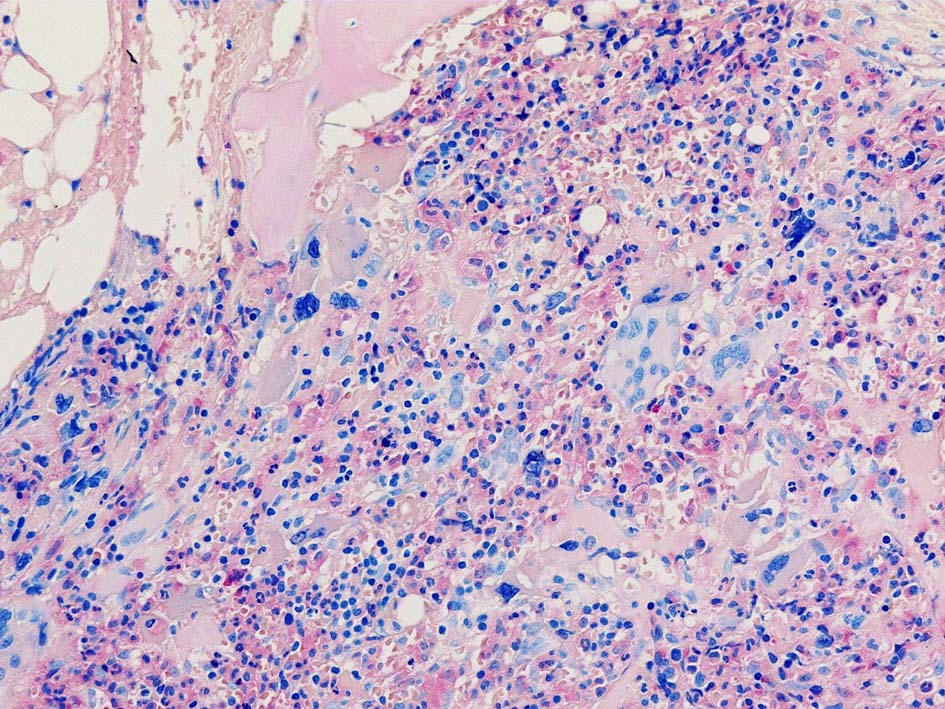

Case01; Meylofibrosis, overt fibrosis

77year-old female. 40歳時polycythemia veraと診断されていた.

[注] この症例は詳細は不明であるが, 過去にPVと診断されているため, PVに伴う二次性のmyelofibrosisの診断になる.

黒染する弾性線維の増生のほか, 赤く染まる膠原線維の増生が確認される. MF-2 fibrosis. 鍍銀染色の核染色をすると膠原線維の赤染がわからなくなるので行わない.